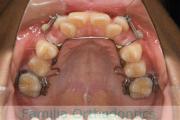

犬歯が八の字になっているので何とかしてほしいということで来院されました。上顎犬歯が左右とも前歯の方に向いていて、一期治療でまずは萌出誘導を行いました。

二期治療は、出っ歯の要素が強かったため、上顎のみ第二小臼歯を抜歯しています。

二期治療は2年強、25回程度の通院が必要でした。犬歯の埋伏歯は、うまく出すことができない場合があったり、出す際に周囲の歯の歯根に傷をつけるリスクがあったりします。